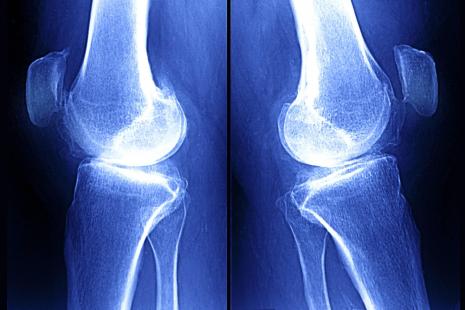

Des chercheurs ont identifié pour la première fois deux molécules prometteuses qui pourraient constituer des biomarqueurs sériques de destruction cartilagineuse liée à l’arthrose précoce. La concentration sérique de deux micro-ARN non codants a été trouvée associée à une destruction modérée du cartilage chez 30 patients, un an après qu’ils ont eu un traumatisme du genou (lésion du ligament croisé antérieur).